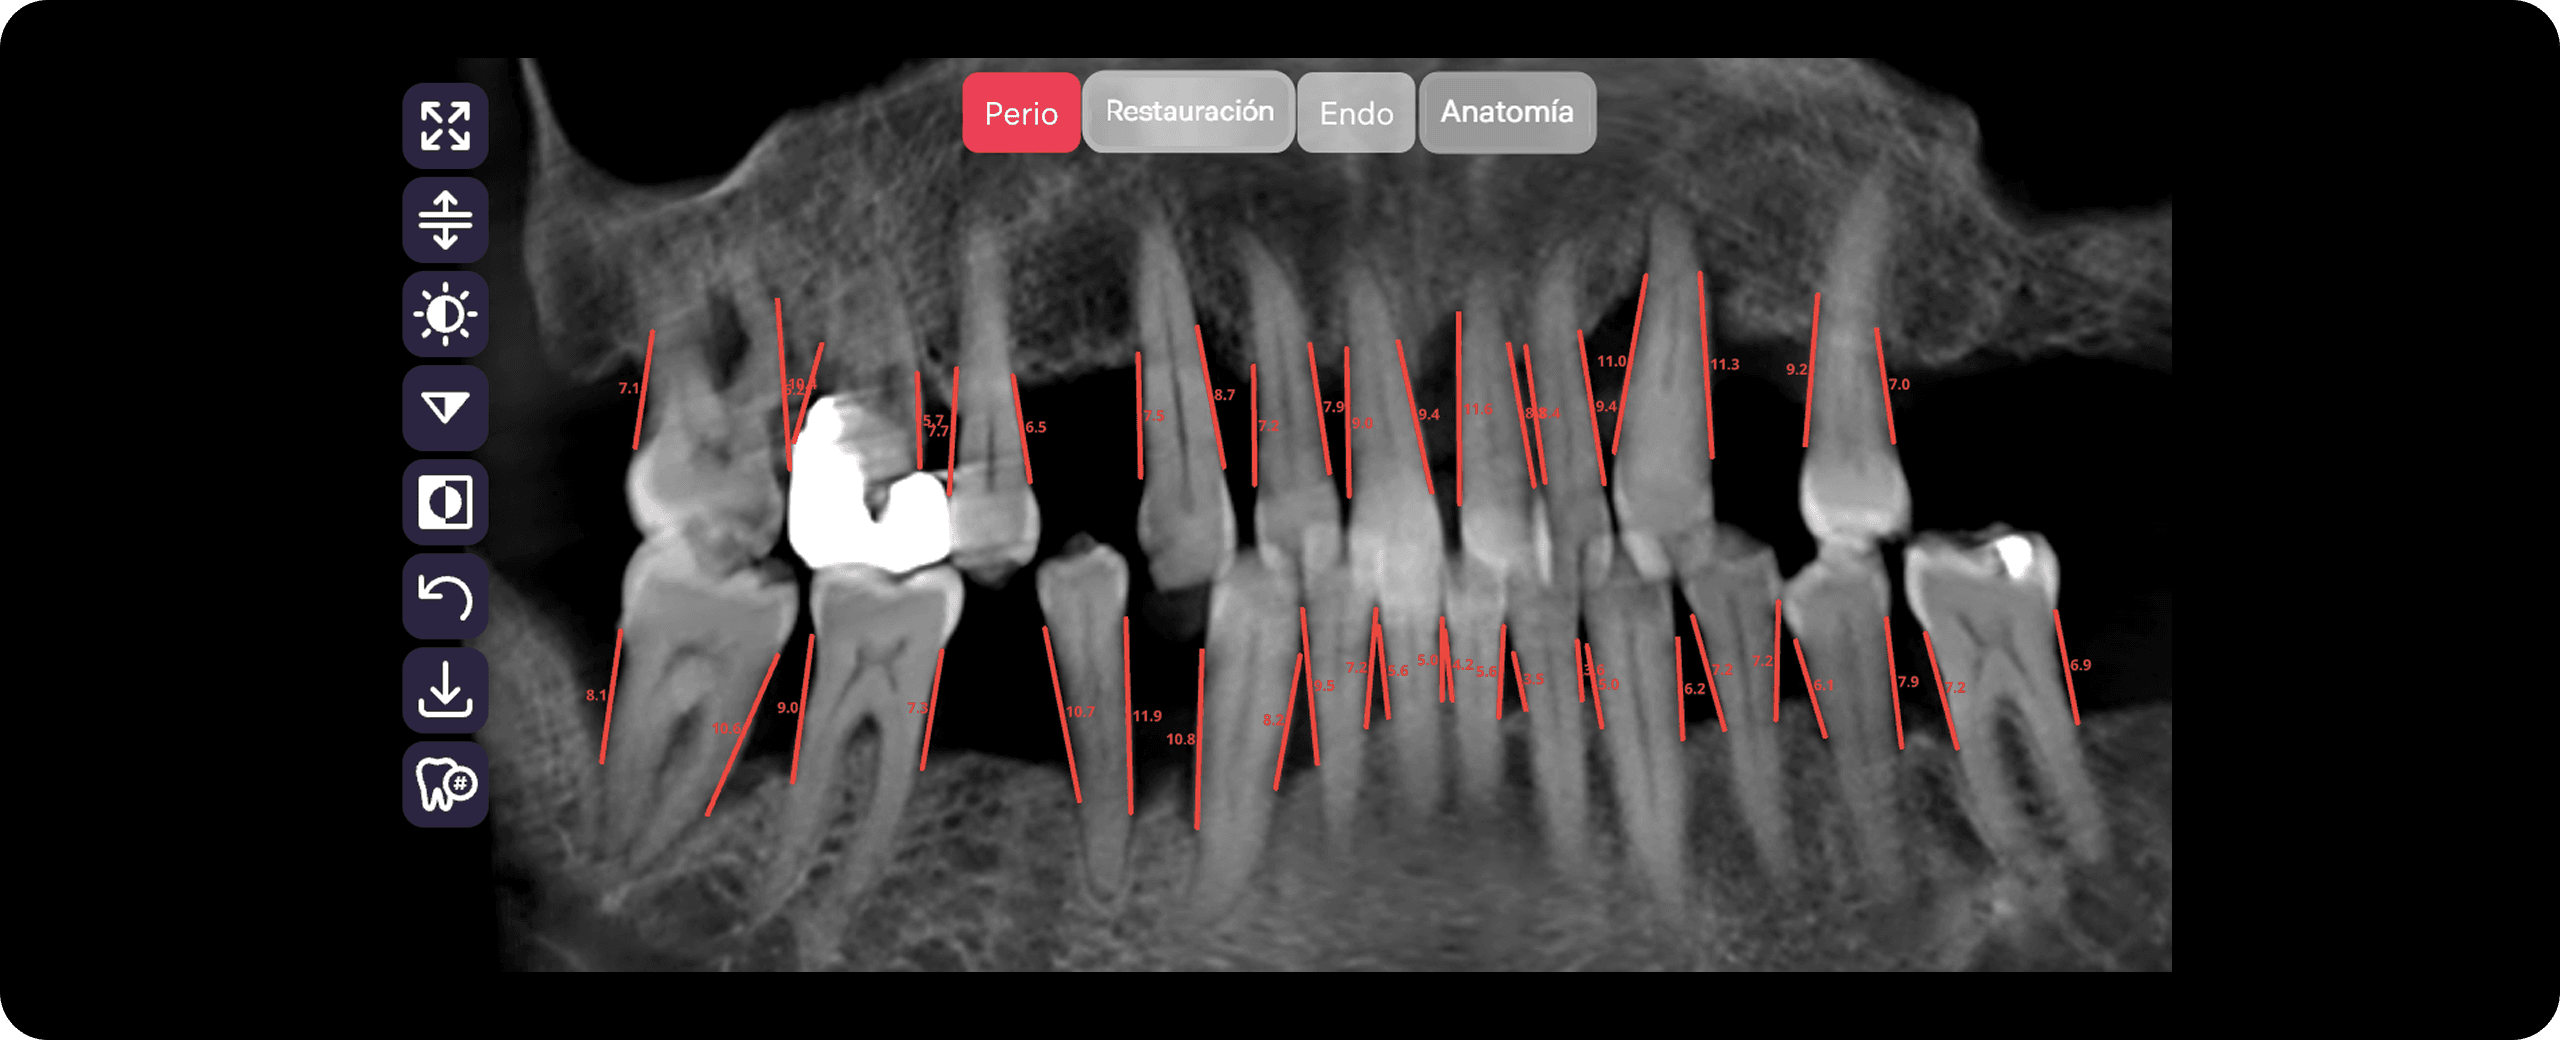

Diagnocat analiza imágenes radiológicas, simplifica la comunicación médico-paciente y motiva al paciente a iniciar el tratamiento.

Diagnocat simplifica las consultas iniciales, optimiza el trabajo en equipo y proporciona informes analíticos para la gestión.